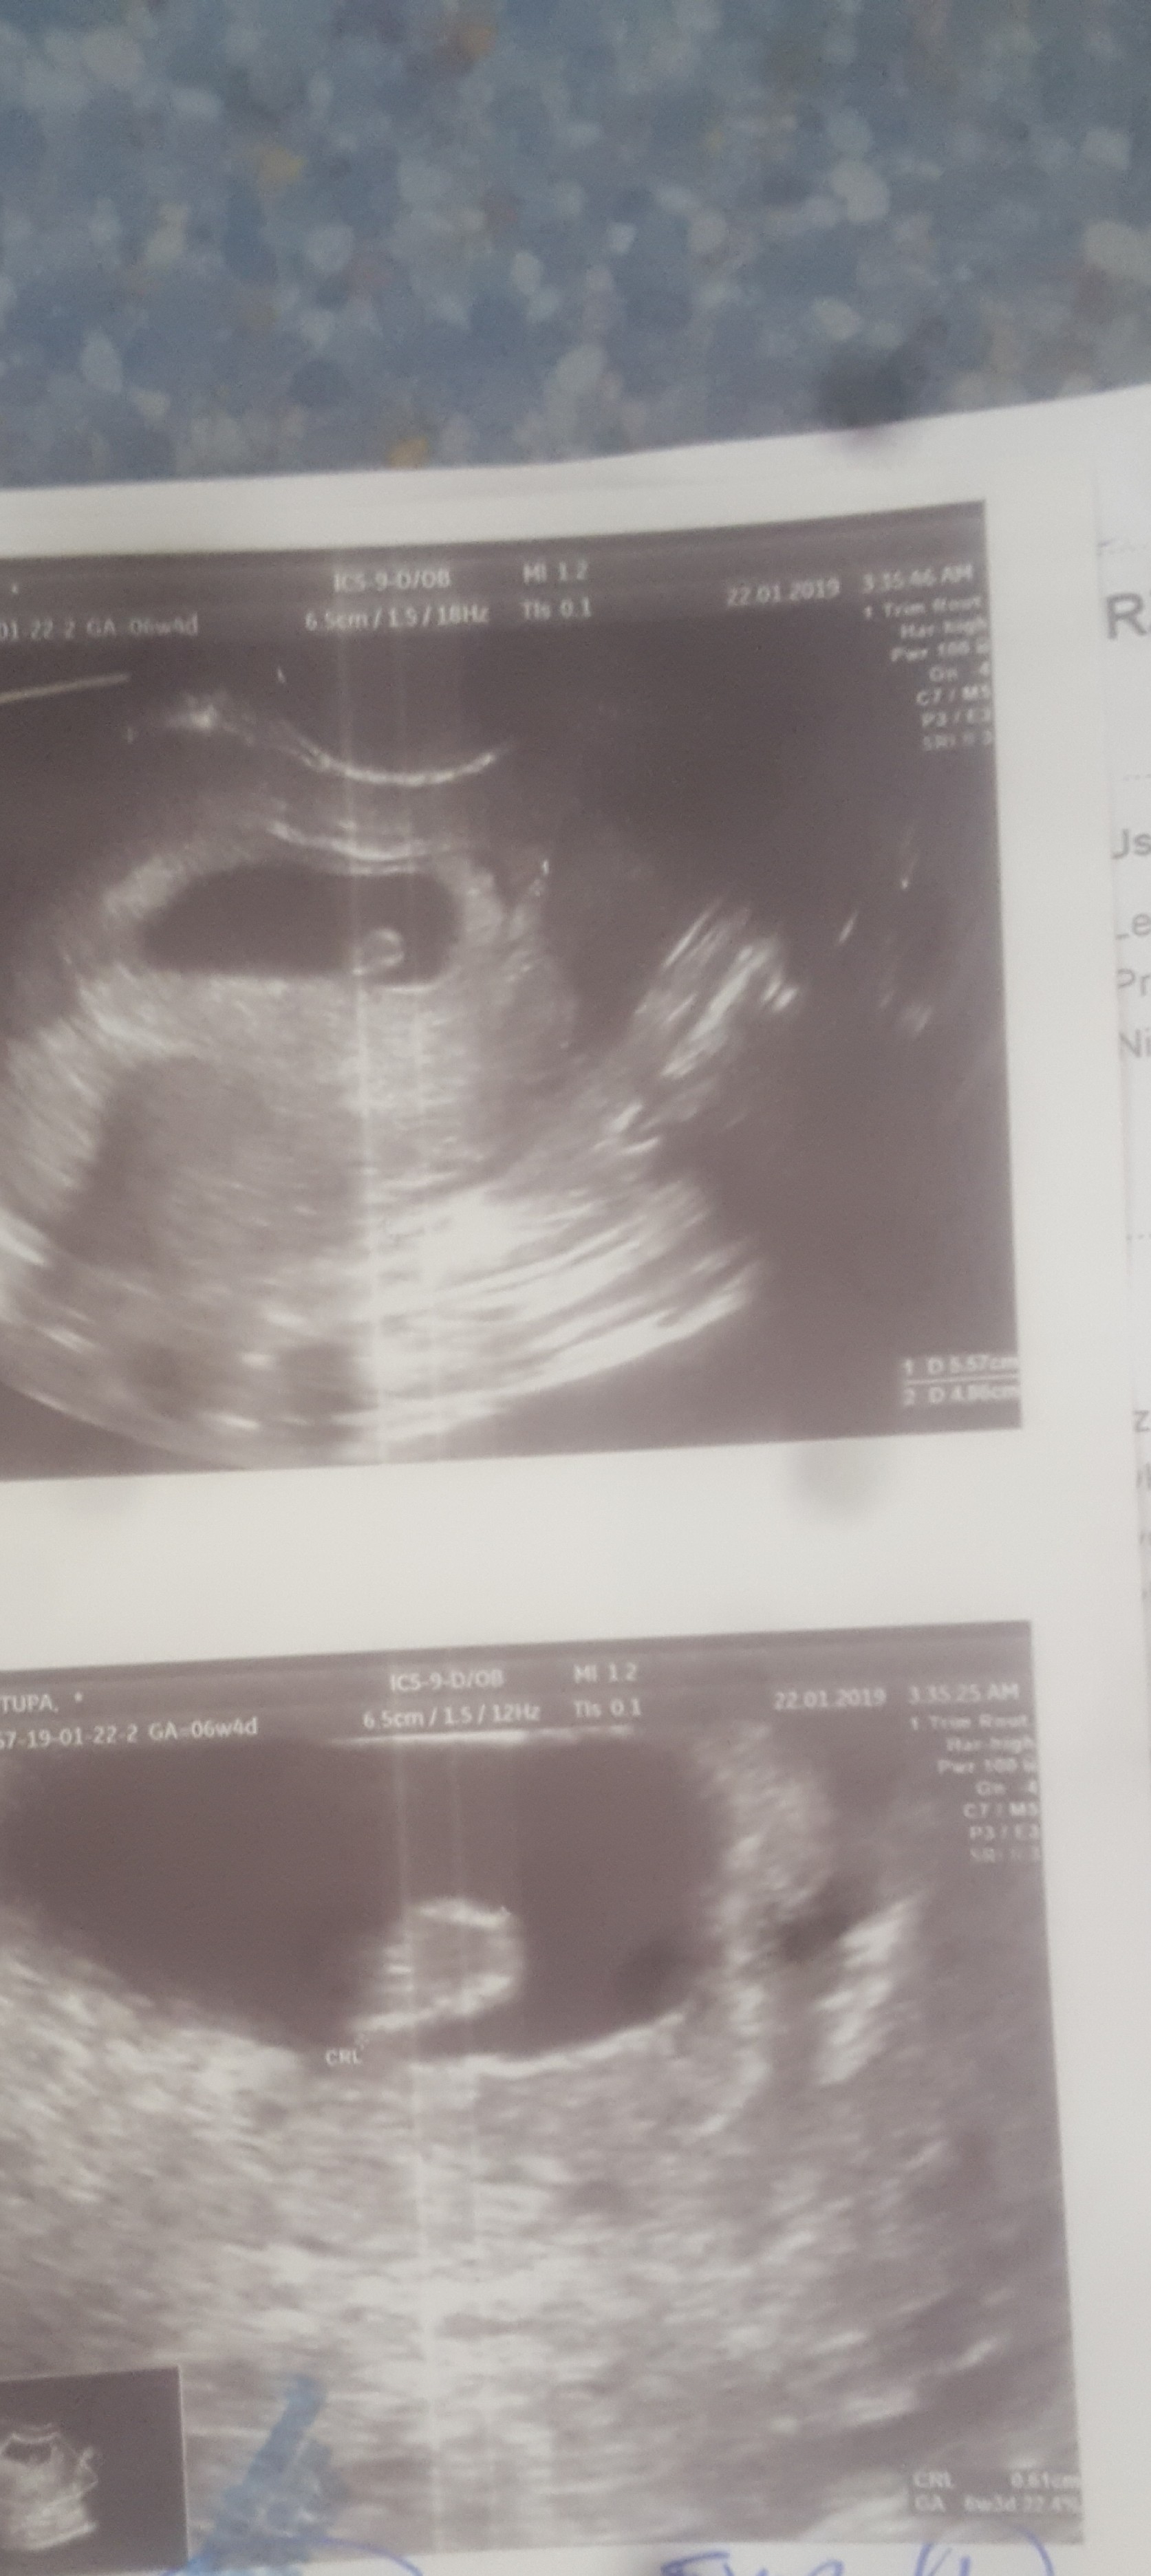

mi rowniez cos sie jeść nie chce, ale to moze przez to szpitalne jedzenie... udalo mi sie wyprosic zdjecie malucha. Wedlug daty ostatniej miesiaczki 6tydz.+4dni. I chyba sie zgadza bo lekarz nic nie mówił o innym wieku ciąży tylko ze dobrze się rozwija. Slaba jakosc, niestety mam zepsuty aparat..Zobacz załącznik 936656

Dokładnie, teraz już pójdzie z górkiNajgorsze już za mną, ważne ze z dzidzią wszystko w porzadkumam takie pytanko, czy gdzies na tym usg jest napisane jak duza jest juz dzidzia? Z calego stresu nie zadalam tak waznego pytania.

Znalazlam, dziękuję!Dokładnie, teraz już pójdzie z górkiszukaj wymiaru CRL